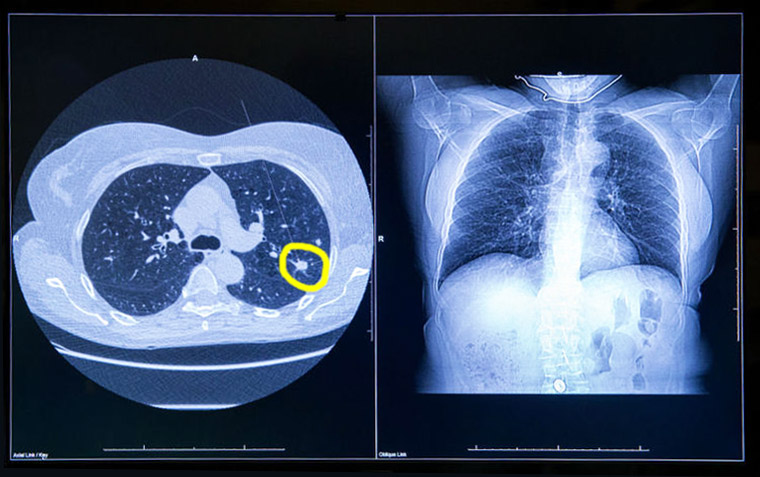

Resultados de la implementación del tamizaje para cáncer de pulmón